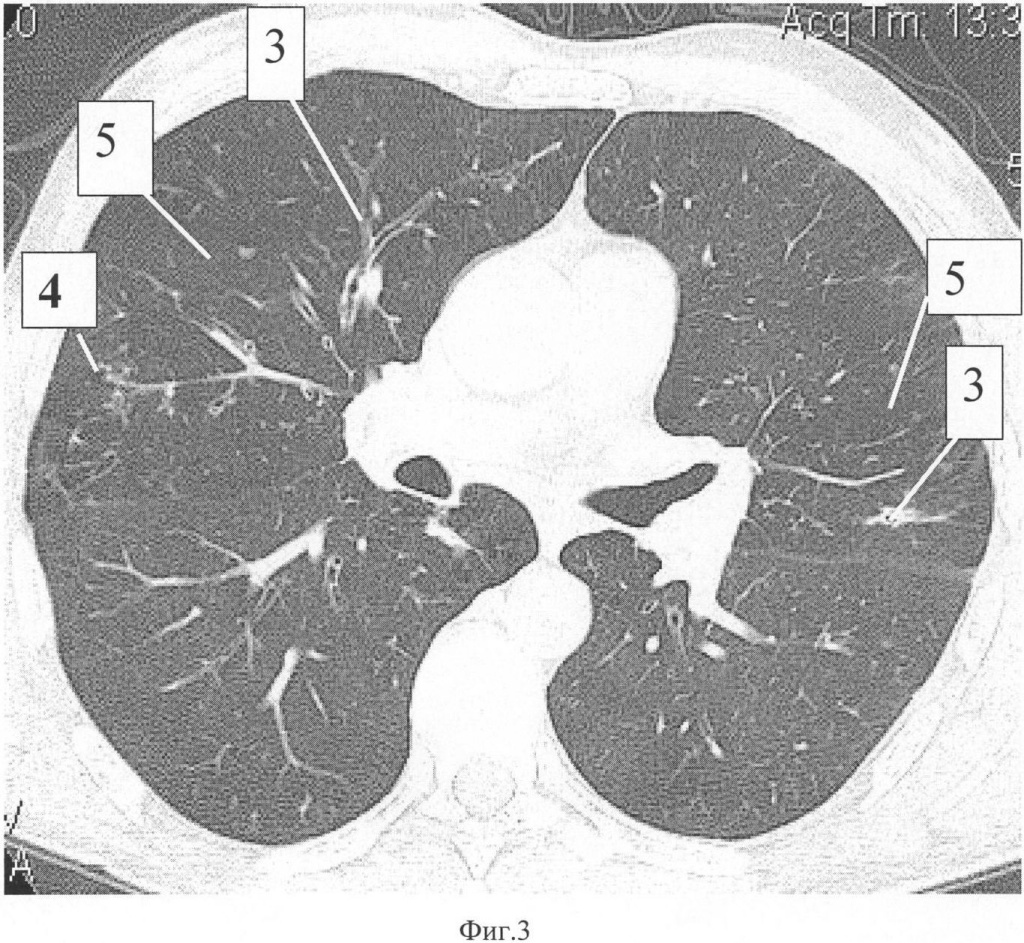

На фиг.1 представлено изображение радиоактивной метки, расположенной на средней трети ключицы в совмещенном трехмерном изображении легких, на фиг.2 представлен аксиальный срез легких на однофотонном компьютерном томографе, где видны участки редуцированного кровотока, на фиг.3 представлен аксиальный срез легких на компьютерном томографе того же уровня, как на ОФЭКТ, где видны участки наибольшего поражения легочной паренхимы, на фиг.4 представлено совмещенное изображение аксиального среза легких.

При компьютерно-томографическом исследовании органов грудной полости с дальнейшим построением реформации изображения в области верхушек обоих легких определялись субплевральные наслоения. В S 4, 5 обоих легких, больше справа, определялись расширенные просветы бронхов с уплотненными стенками 3 (фиг.3), визуализировались также множественные, заполненные содержимым, бронхиолы 4, создающие симптом «дерева в почках» (фиг.3). Воздушность легочной ткани также была диффузно повышена во всех отделах легких за счет панлобулярной и центриацинарной эмфиземы 5 (фиг.3).